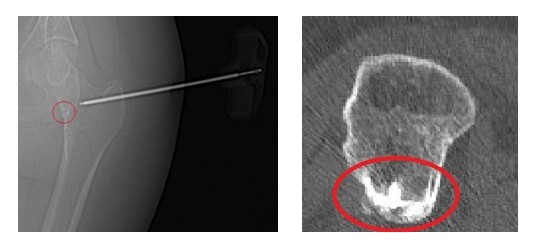

- Радиофреквентна аблация (RFA) – миниинвазивен метод, позволяващ достигане до лезията чрез игла и минимален кожен достъп, под прецизен компютър-томографски контрол.

Процедурата се извършва след внимателно планиране и преминаване през т.нар. „safe zones“ за безопасен достъп до костта. Нидусът се обработва чрез термична аблация и коагулация на патологичните клетки, продуциращи простагландини.

Интервенцията бе извършена от д-р Станислав Балев под локална анестезия и КТ-контрол.